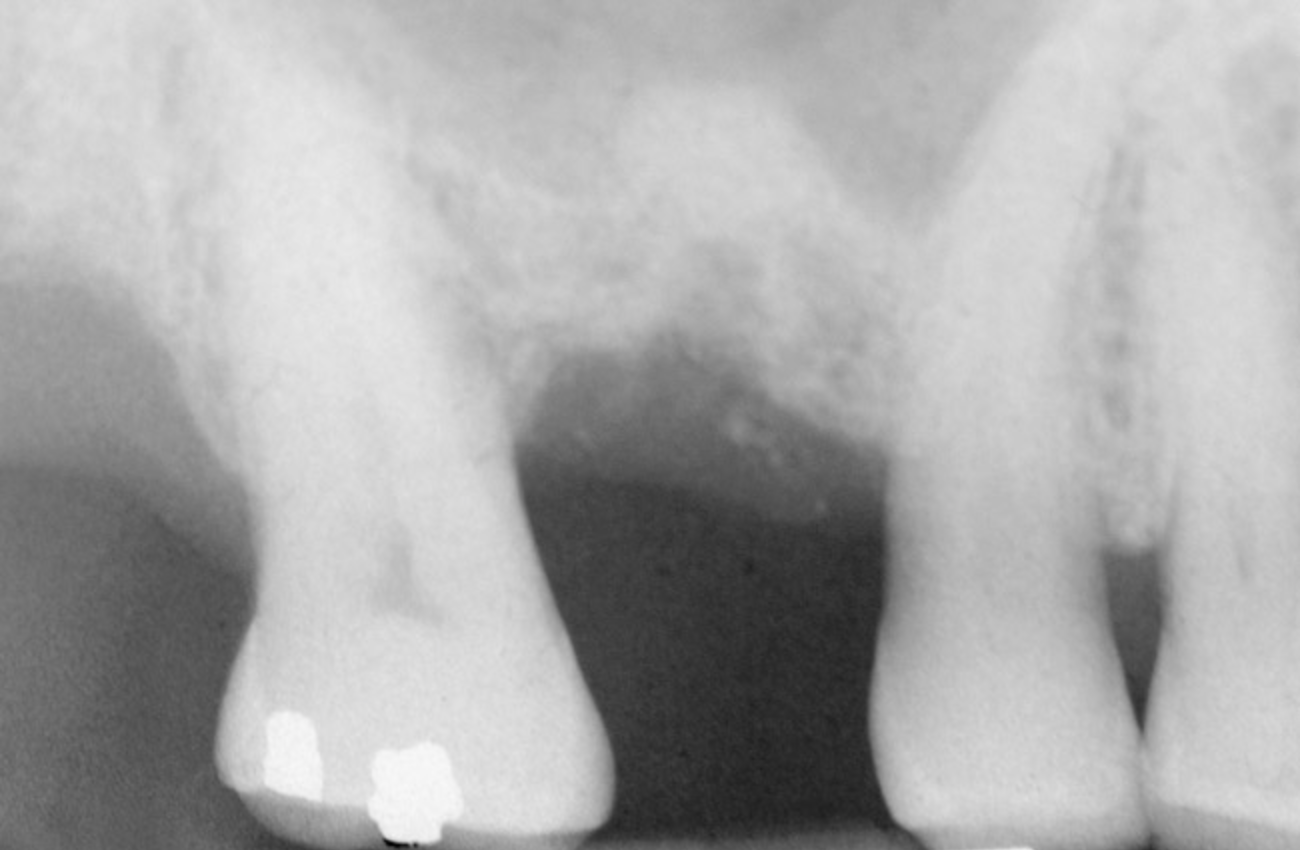

First, a periapical radiograph is taken to determine the amount of bone subantrally. It should be noted that a periapical film has an average error of 14%.23 Therefore, it is advantageous to take the radiograph in a manner that includes a marker (5-mm wide ball bearing) in order to be able to calculate the magnitude of radiographic error (Figure 1).

Figure 1  At tooth site No. 14, a periapical radiograph was taken with the long-cone paralleling technique. The radiographic ball marker measured 5.8 mm while its actual diameter is 5 mm. The enlargement is 0.8 mm, therefore the magnification error is 0.8/5 = 16%. By correcting for this error, a closer approximation of the amount of bone from the osseous crest to the sinus floor can be made.

Figure 1